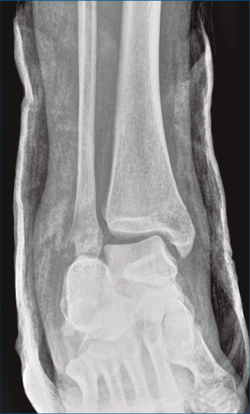

Se trata de un varón de 19 años que ingresa en reanimación tras precipitarse desde una altura de aproximadamente 10 metros. El paciente presenta una fractura estallido de L3 con afectación del canal medular junto con una fractura del vértice inferior de L4, así como una fractura luxación de calcáneo, asociada a una fractura del maléolo peroneo y del maléolo tibial posterior (Figuras 1 a 6) diagnosticadas mediante TC total body (por eso no se dispone de radiografías simples al momento del ingreso). Como podemos comprobar, se trata de una fractura de doble trazo de tipo hundimiento/depresión de la carilla articular (Figuras 5 y 6).

Figura 5. Fractura maléolo peroneo, luxación astrágalo, fractura de doble trazo en calcáneo.

Figura 8. Radiografía anteroposterior de tobillo, inclinación lateral del astrágalo, ocupación del espacio subperoneo, fractura maléolo peroneo y apertura de sindesmosis.